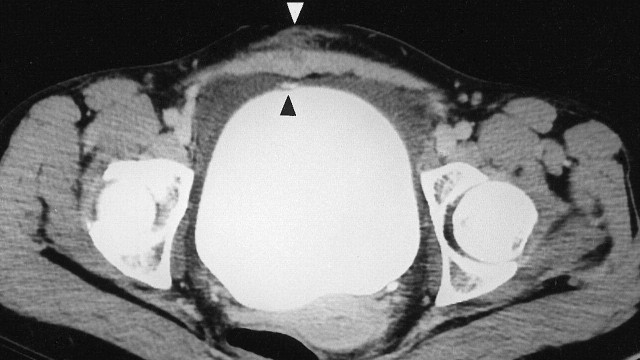

Bệnh nhân bị chấn thương bàng quang thường có nhiều triệu chứng sốc đa chấn thương như thủng hoặc vỡ bàng quang. Vì vậy, cần chẩn đoán sớm và điều trị kịp thời chấn thương bàng quang để giảm tỷ lệ tử vong và biến chứng do chấn thương gây ra.